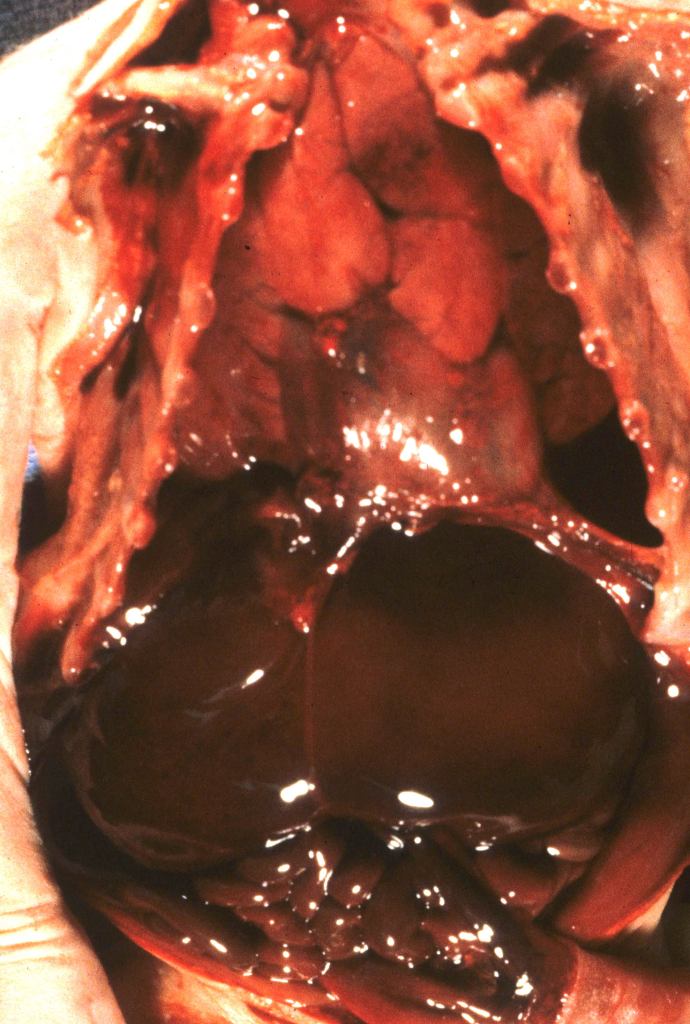

Subcapsular Hematoma: On opening the abdomen, usually in preterm infants, there may be a hematoma, usually relatively new, beneath the anterior margin. The subcapsular connective tissue is weak and connected to the sinusoids as the likely source of the hemorrhage. It is possible to produce such a hematoma postmortem with pressure on the liver, and possibly some are produced by delivery trauma. However, there are factors that suggest a predelivery origin such as the association with perinatal fetal sepsis1. Occasionally they may rupture and cause a large hemoperitoneum (Fig 1).